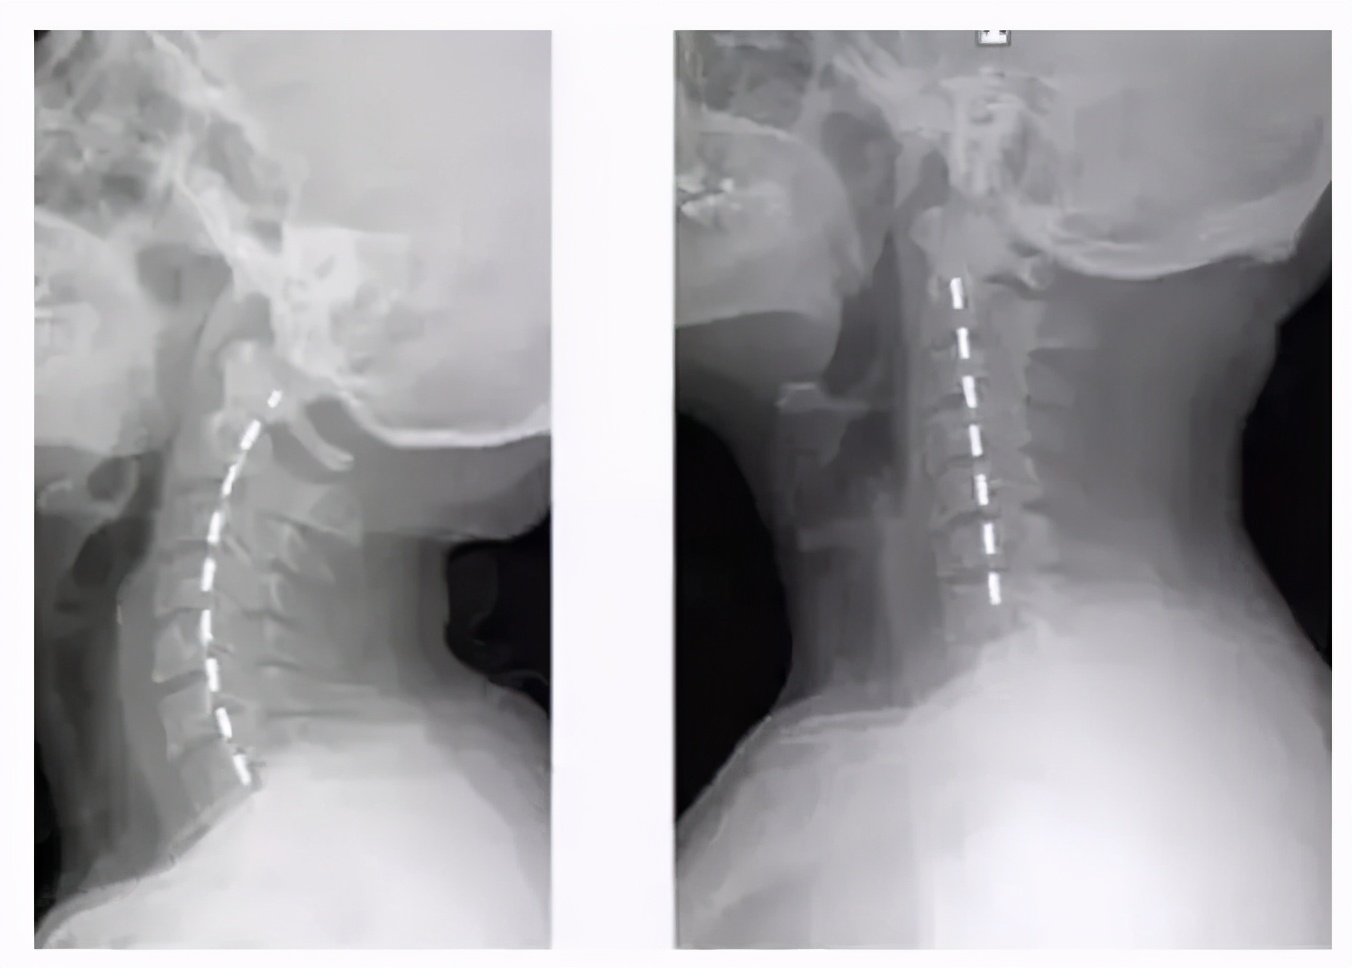

看下面一张图片,一般情况下我们的颈椎都是有弯度的。

但是并不是我们想象中的那样笔直,颈椎是有弧度的,而这种弧度向前弯曲,像一个拉开的弓一样。